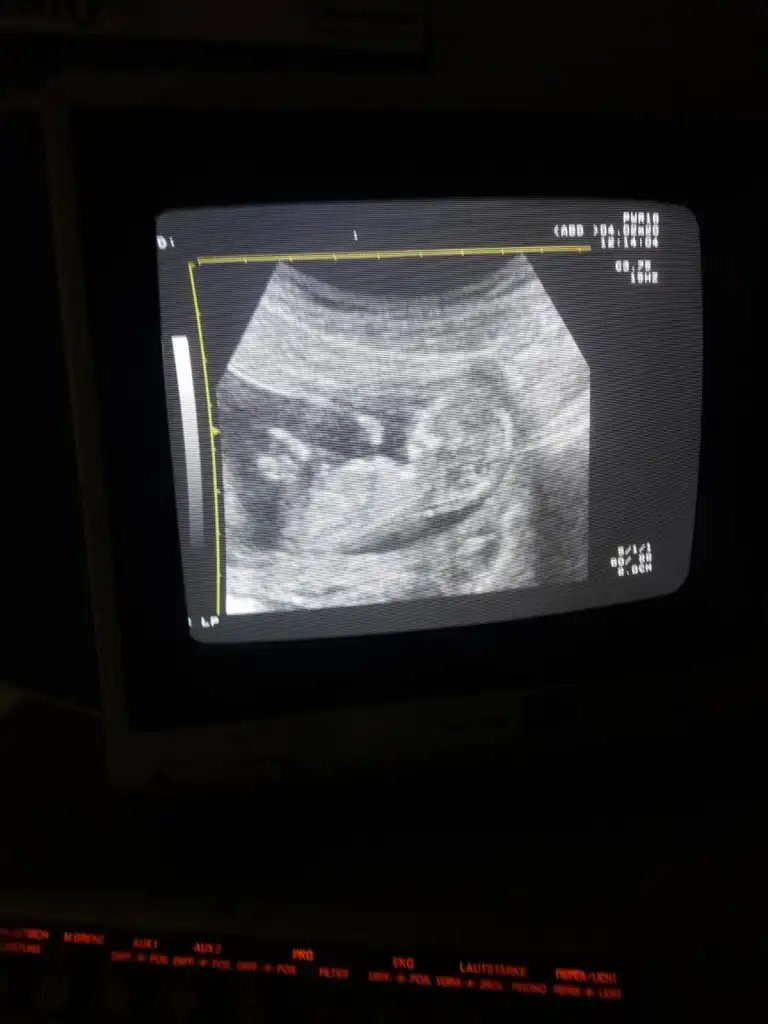

11 haftalikken kiz demistiniz ve Evet 18+4 te doktor kiz bebek dedi ☺Kız gibi diyorum net degil usg başka varmı 12+ hafta usgde paylaşın

Kız gibi tam net degil başka ush paylaşın 12 de olır13+1 sizce ?

Kız gibi gibi kaç haftalık bu usgBu arkası dönük olmazmi![]()

Başka usg varmı çok net değil diklik görünüyor sanki erkek gibi emin olamıyorum12 haftalık acaba cinsiyet tahmininde bulunabilir misiniz

Başka usg varmı çok net değil diklik görünüyor sanki erkek gibi emin olamıyorum

Yaa yukardan arkadaş bana mesaj yazıyorduYani şu gördüğüm nub ise dik görünüyor bacaklar yukarda nubunu değiştirmiyorsa pozisyon erkek gibiEki Görüntüle 2584968